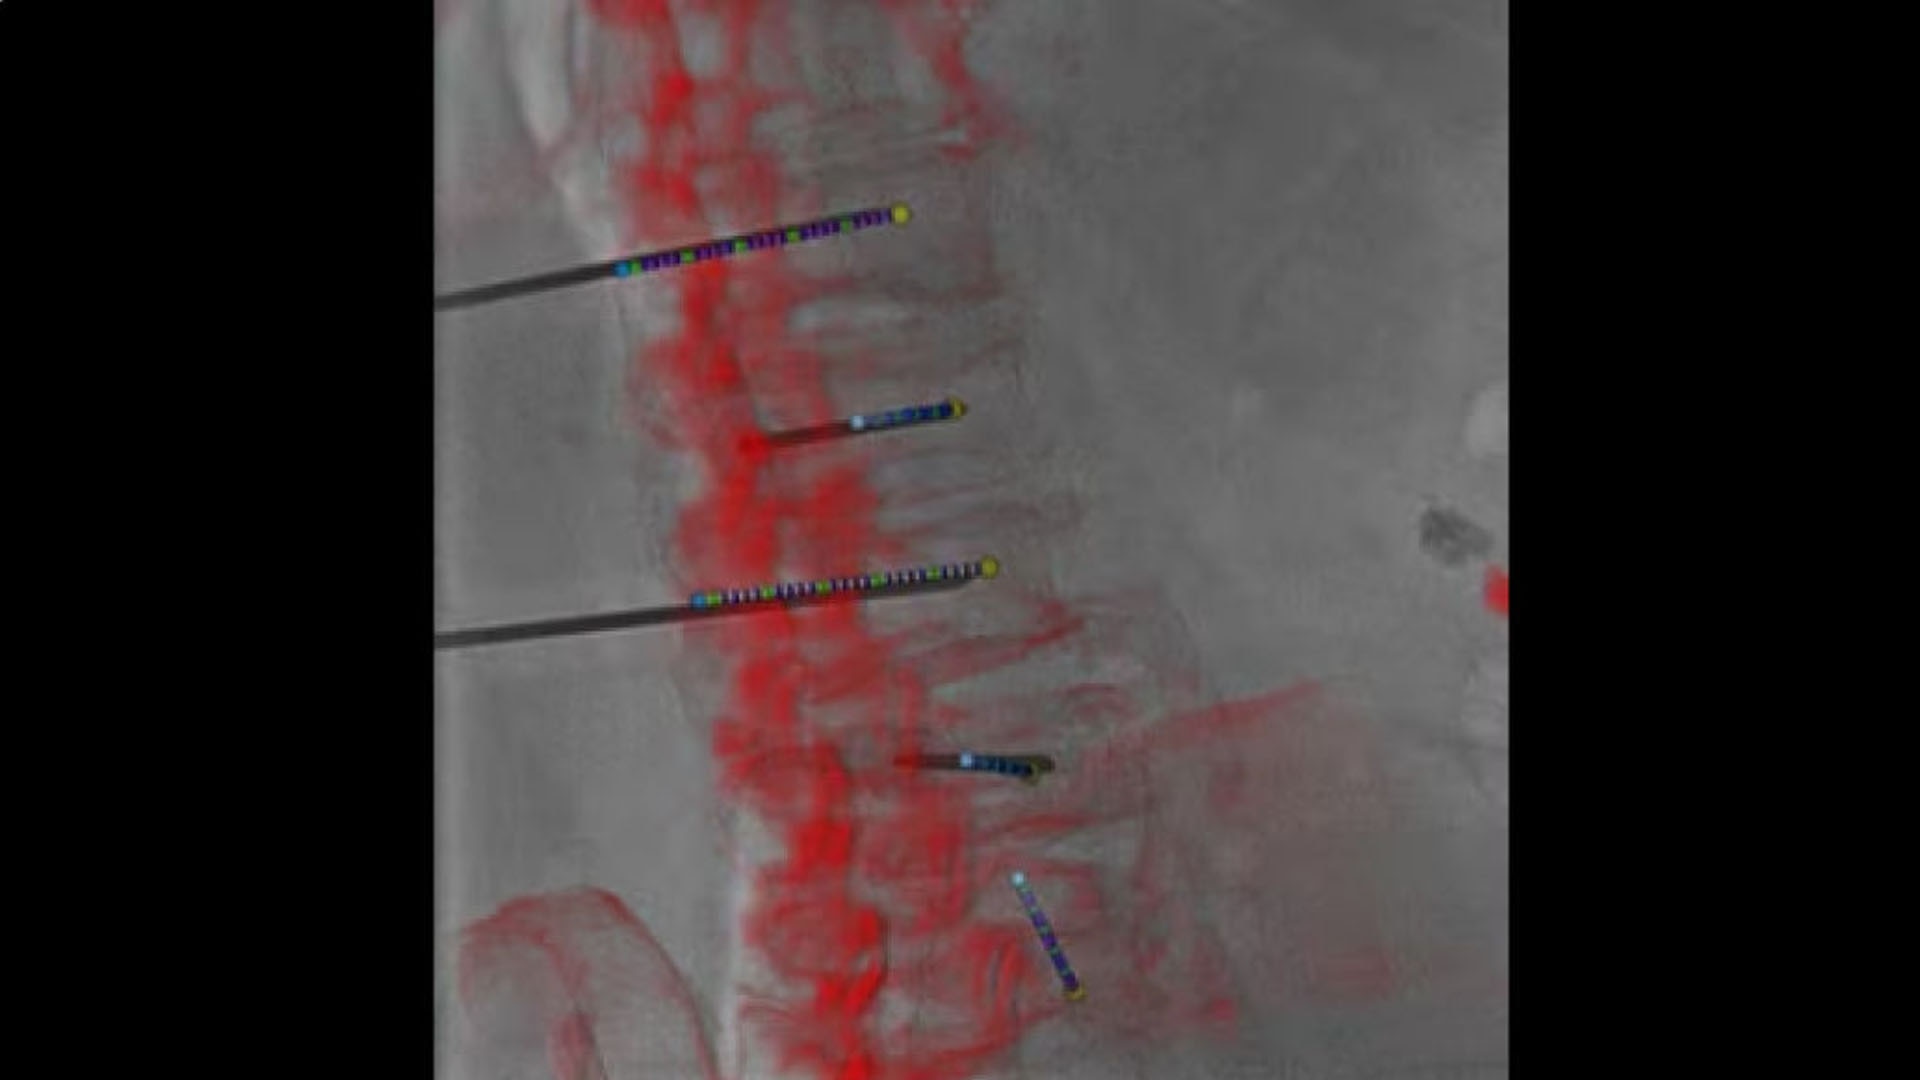

Access

Review needle placement

All at table side, reconstruct a needle in 3D with 2 fluoroscopic images with accuracy and to review the location of the reconstructed needle on the 3D anatomy.

hero_sticky_scrolling_3-ci-en